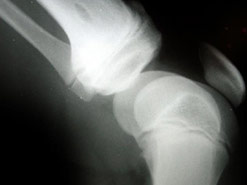

Osteoporosis

One in two women and one in five men in the UK over the age of 50 will break a bone because of osteoporosis.

Losing bone density is a natural part of the ageing process but what makes some people more susceptible to porous bones than others?

Being post-menopausal, taking certain prescription drugs, smoking and drinking are all risk factors for developing osteoporosis.